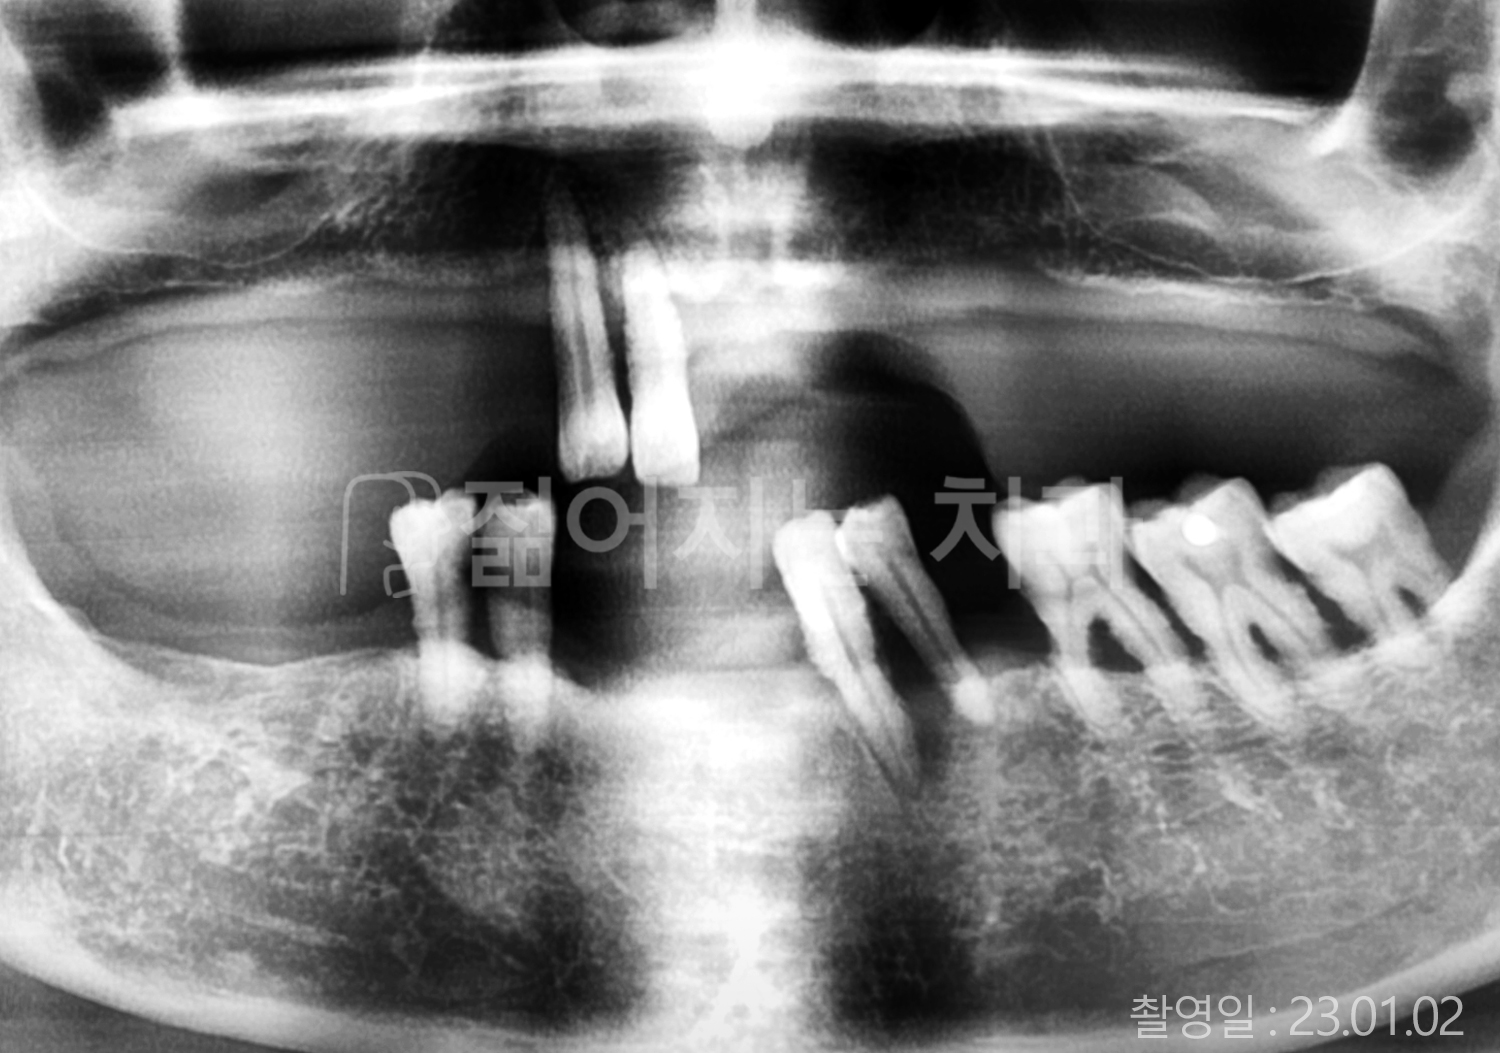

• 40대 전체치아 10개 이상 임플란트

• 70대 당뇨 전체치아 10개 이상 임플란트

• 60대 전체치아 10개 이상 임플란트

• 60대 고혈압, 당뇨, 고지혈증 전체치아 10개 이상 임플란트

• 50대 전체치아 10개 이상 임플란트

• 70대 고혈압, 당뇨 전체치아 10개 이상 임플란트

• 60대 고혈압 전체치아 10개 이상 임플란트

• 50대 고혈압, 당뇨, 고지혈증 전체치아 10개 이상 임플란트

• 60대 고혈압, 고지혈증 전체치아 10개 이상 임플란트